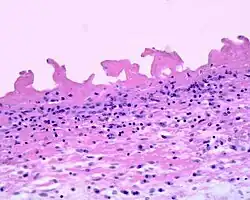

Pericarditis fibrinosa

Fibrinous pericarditis is an exudative inflammation. The pericardium is infiltrated by the fibrinous exudate. This consists of fibrin strands and leukocytes. Fibrin describes an amorphous, eosinophilic (pink) network. Leukocytes (white blood cells; mainly neutrophils) are found within the fibrin deposits and intrapericardic. Vascular congestion is also present. Inflammatory cells do not penetrate the myocardium (as is seen with other presentations of pericarditis), and as a result, this particular variant does not present with diffuse ST elevation on ECG (a classic sign of pericarditis known as stage I ECG changes which are seen with other causes)[1] because the inflammatory cells do not penetrate the myocardium. To naked eye examination, this pathology is referred to as having a "Bread and Butter Appearance".